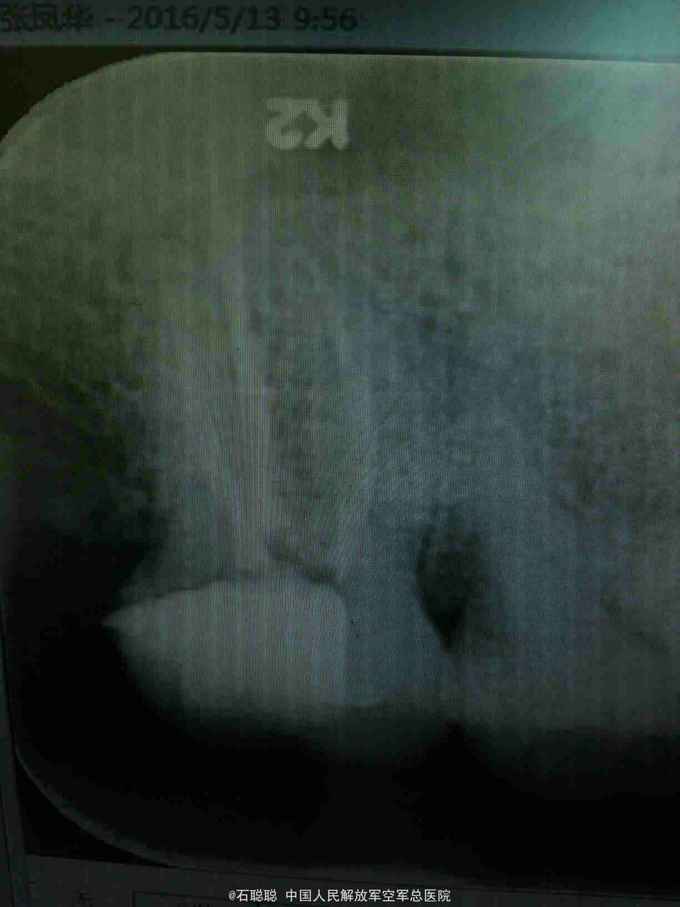

诊断:右上7慢性牙髓炎急性发作 治疗计划:右上7RCT后冠修复 处置:右上7碧蓝局麻下开髓,去腐,揭顶,探及近颊、远颊、腭侧三个根管口,略疏通,见血性渗出,冲洗,干燥,置失活剂,氧化锌暂封 一周后复诊:诉无不适 查:右上7氧化锌完整在位,叩痛-,不松动,牙龈未见异常 处置:右上7去除氧化锌暂封,测工作长度,近颊=远颊=19mm,扩大至30#,腭根=21mm,扩大至35#,冲洗,干燥,置CP棉球,氧化锌暂封 一周后复诊:诉无不适 查:右上7氧化锌完整在位,叩痛-,不松动,牙龈未见异常 处置:右上7去除氧化锌暂封,试主尖,冲洗、干燥,冷侧压充填,置干棉球,氧化锌暂封 嘱:勿用患牙咀嚼 一周后择期修复